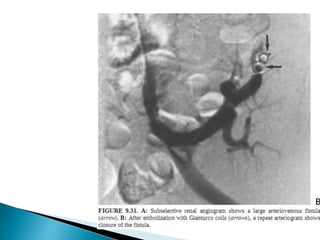

3. Renal AVF

 ESRD , usually undergo biopsy  AVF/pseudo-

aneurysm.